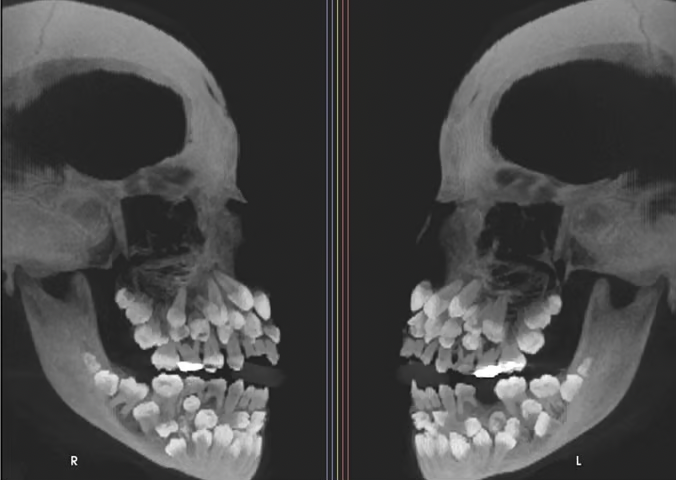

11세 소녀 입 안에서 치아가 무려 81개나 발견돼 학계에 충격을 주고 있다. 지난 15일 VN익스프레스 등 외신은 브라질에 사는 11세 소녀가 위쪽 유치 1개를 뽑기 위해 병원을 찾았는데 엑스레이 촬영 결과 소녀의 입안에서 유치 18개와 영구치 32개, 과잉치 31개 등 총 81개 치아가 발견됐다고 보도했다.

일반적으로 성인 기준 32개인 정상 치아 수를 넘는 추가 치아가 발견되는 것을 '다발성 과잉치증(multiple hyperdontia)'으로 부른다. 이 질환은 잇몸 속에 치아가 매복돼 있어 정상 치아의 맹출(잇몸 위로 나는 과정)을 방해하거나 치아 배열이 어긋나는 등의 문제를 일으킬 수 있다. 또한 매복된 과잉치 주변에 물혹이 생기는 등 다양한 문제가 유발될 수 있다. 다발성 과잉치증은 선천적인 것으로 대개 1~2개의 과잉치만 발견되는 경우는 종종 있다. 일반적으로 합병증을 유발할 가능성이 있는 과잉치는 발치를 권장하며, 특히 어린아이의 경우 영구치 맹출에 방해가 되지 않도록 조기에 발치하는 것이 좋다. 발치 후에는 치아 배열을 위해 교정 치료가 필요할 수 있다. 다만 이번 사례처럼 30개가 넘는 과잉치가 확인된 사례는 전 세계적으로도 매우 드물다. 해당 사례는 브라질 미나스제라이스주 주이스지포라 연방대학교 치과병원 연구팀이 진료 중 확인한 것으로 미국 치과교정·악안면외과학회지에 보고됐다.

연구팀은 정밀 영상 검사를 통해 치아의 정확한 위치를 파악하고 유전 질환과 연관된 것은 아닌지 확인하기 위해 관련 유전자 검사도 함께 진행했다. 보통 다발성 과잉치는 쇄골두개이형성증, 가드너 증후군, 구개열 등을 동반하는 경우가 많지만, 검사 결과 소녀는 이 질환들에 해당하지 않았다.

추가로 진행된 염색체 검사에선 9번 염색체 일부 구간이 뒤바뀌는 구조 이상(염색체 역위)이 발견됐다. 드물게 나타나는 유전적 변이지만 과잉치 발생과 직접적 관련이 있는지는 알 수 없다고 연구팀은 전했다. 일부 과잉치는 잇몸 속에 깊이 묻혀 있거나 정상 치아와 형태가 유사해 정확한 구분이 쉽지 않다. 무작정 발치할 경우 턱뼈 손상 우려도 있다. 이에 연구팀은 치과 교정과, 악안면외과, 치주과, 보철과 등 여러 전문의와 팀을 꾸려 장기적인 치료 계획을 세우고 있는 것으로 전해졌다.